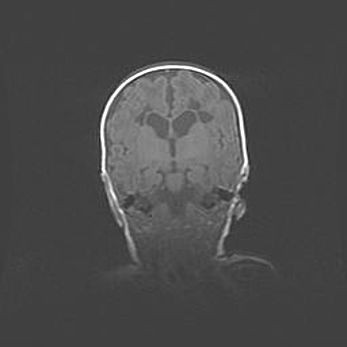

Открытая гидроцефалия.

Возраст: 9 месяцев 12 дней

Вес: 6800 г

Пол: мужской

Окружность головы: 41,5 см

Срок гестации: 28 недель

Гидроцефалия головного мозга у новорожденных имеет характерный признак: опережающий рост окружности головы приводит к визуально хорошо определяемой гидроцефальной форме сильно увеличенного в объёме черепа. Детские неврологи определяют следующие симптомы гидроцефалии у грудничков: выбухающий напряжённый родничок, частое запрокидывание головы, смещение глазных яблок к низу.